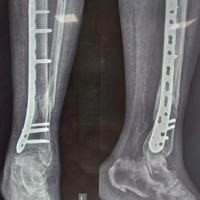

The anterior or posterior two-portal approach is selected based on the location of the osteochondral lesion of the talus (OLT). Patients undergoing the anterior approach were positioned supine position. An anteromedial and anterolateral two-portal approach was made (Fig. 1 and 2). Just medial to the tibialis anterior tendon helps define the anteromedial portal and the anterolateral portal just laterals to the peroneus tertius tendon. Arthroscopic microfracture is a reparative cartilage procedure performed under direct visualization to address OLTs (Fig. 3). For reference, Figure 4 shows osteochondral lesion over the talus.

Figure 4: The above images show osteochondral lesion over the talus.